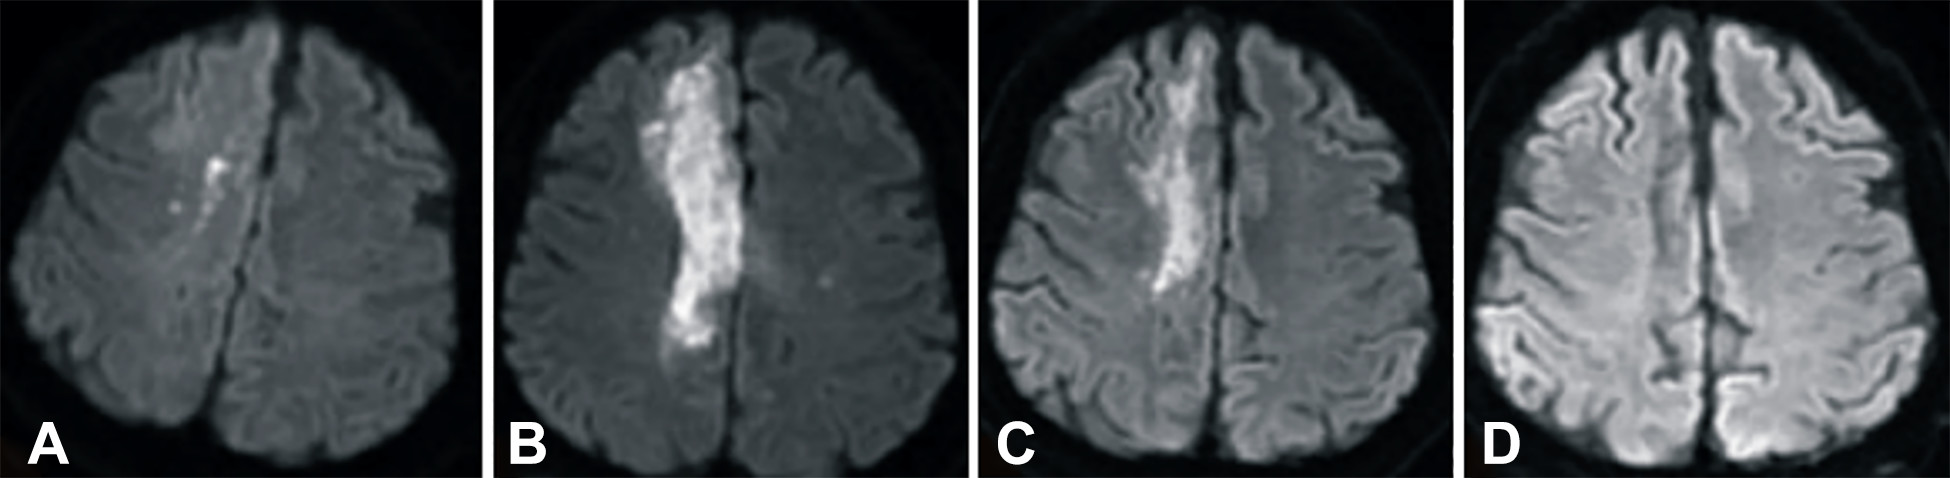

發病后2小時和8天行彌散加權成像(DWI)檢查,發現右側放射冠梗塞(白色信號增加),3個月后梗塞散在,6個月后消失(圖2A-D)。

梗塞發生后2小時、8 天、3 個月和 6個月獲得的T2加權圖像顯示右側放射冠白色強度增加(圖3A-D)。